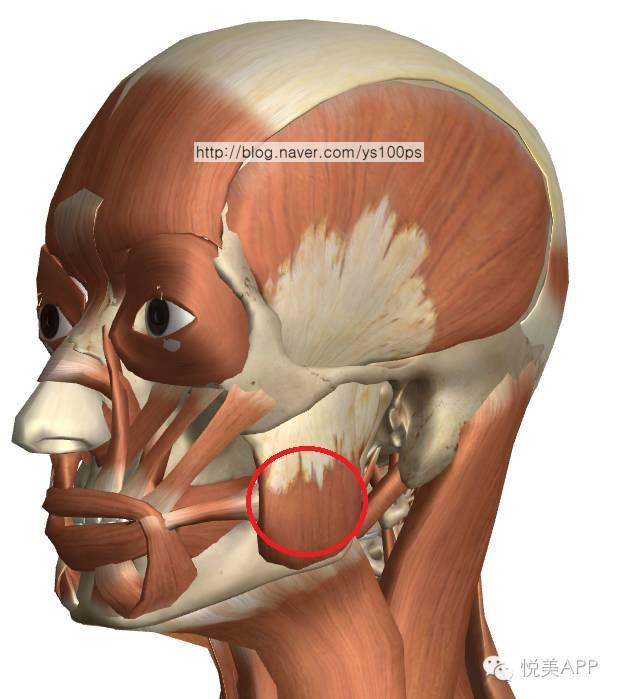

固定 VS 咬肌牵拉

咬肌上端附着于颧骨颧弓的下方和后方,下端附着于下颌角,下颌升支。承担主要的咀嚼功能。

长期的进食咀嚼,咬肌的收缩对颧弓颧骨下方施加持续的张力,是造成颧弓颧骨手术后颧弓骨块下移的主要因素。

目前,在韩国和我国的一些医生理念中:颧弓两端离断,前方需要固定,后方不需要固定。后方靠骨组织周围的骨膜和韧带悬挂,不至于下移。

但咬肌的强大力量长期牵引,仍然造成了以下案例后端骨端的下滑,同时对前方的颧骨固定点形成了杠杆作用,强大的杠杆力使得前方固定点上端裂开。最终使颧弓向后下方旋转,翻转。

以下案例,后端未固定,只把整段骨块内移插入到后方骨端的内侧,但由于术后患者的咬肌运动,牵拉骨块,使得后段本来重叠推进去的骨端弹出,所以面部宽度最终未能缩小。